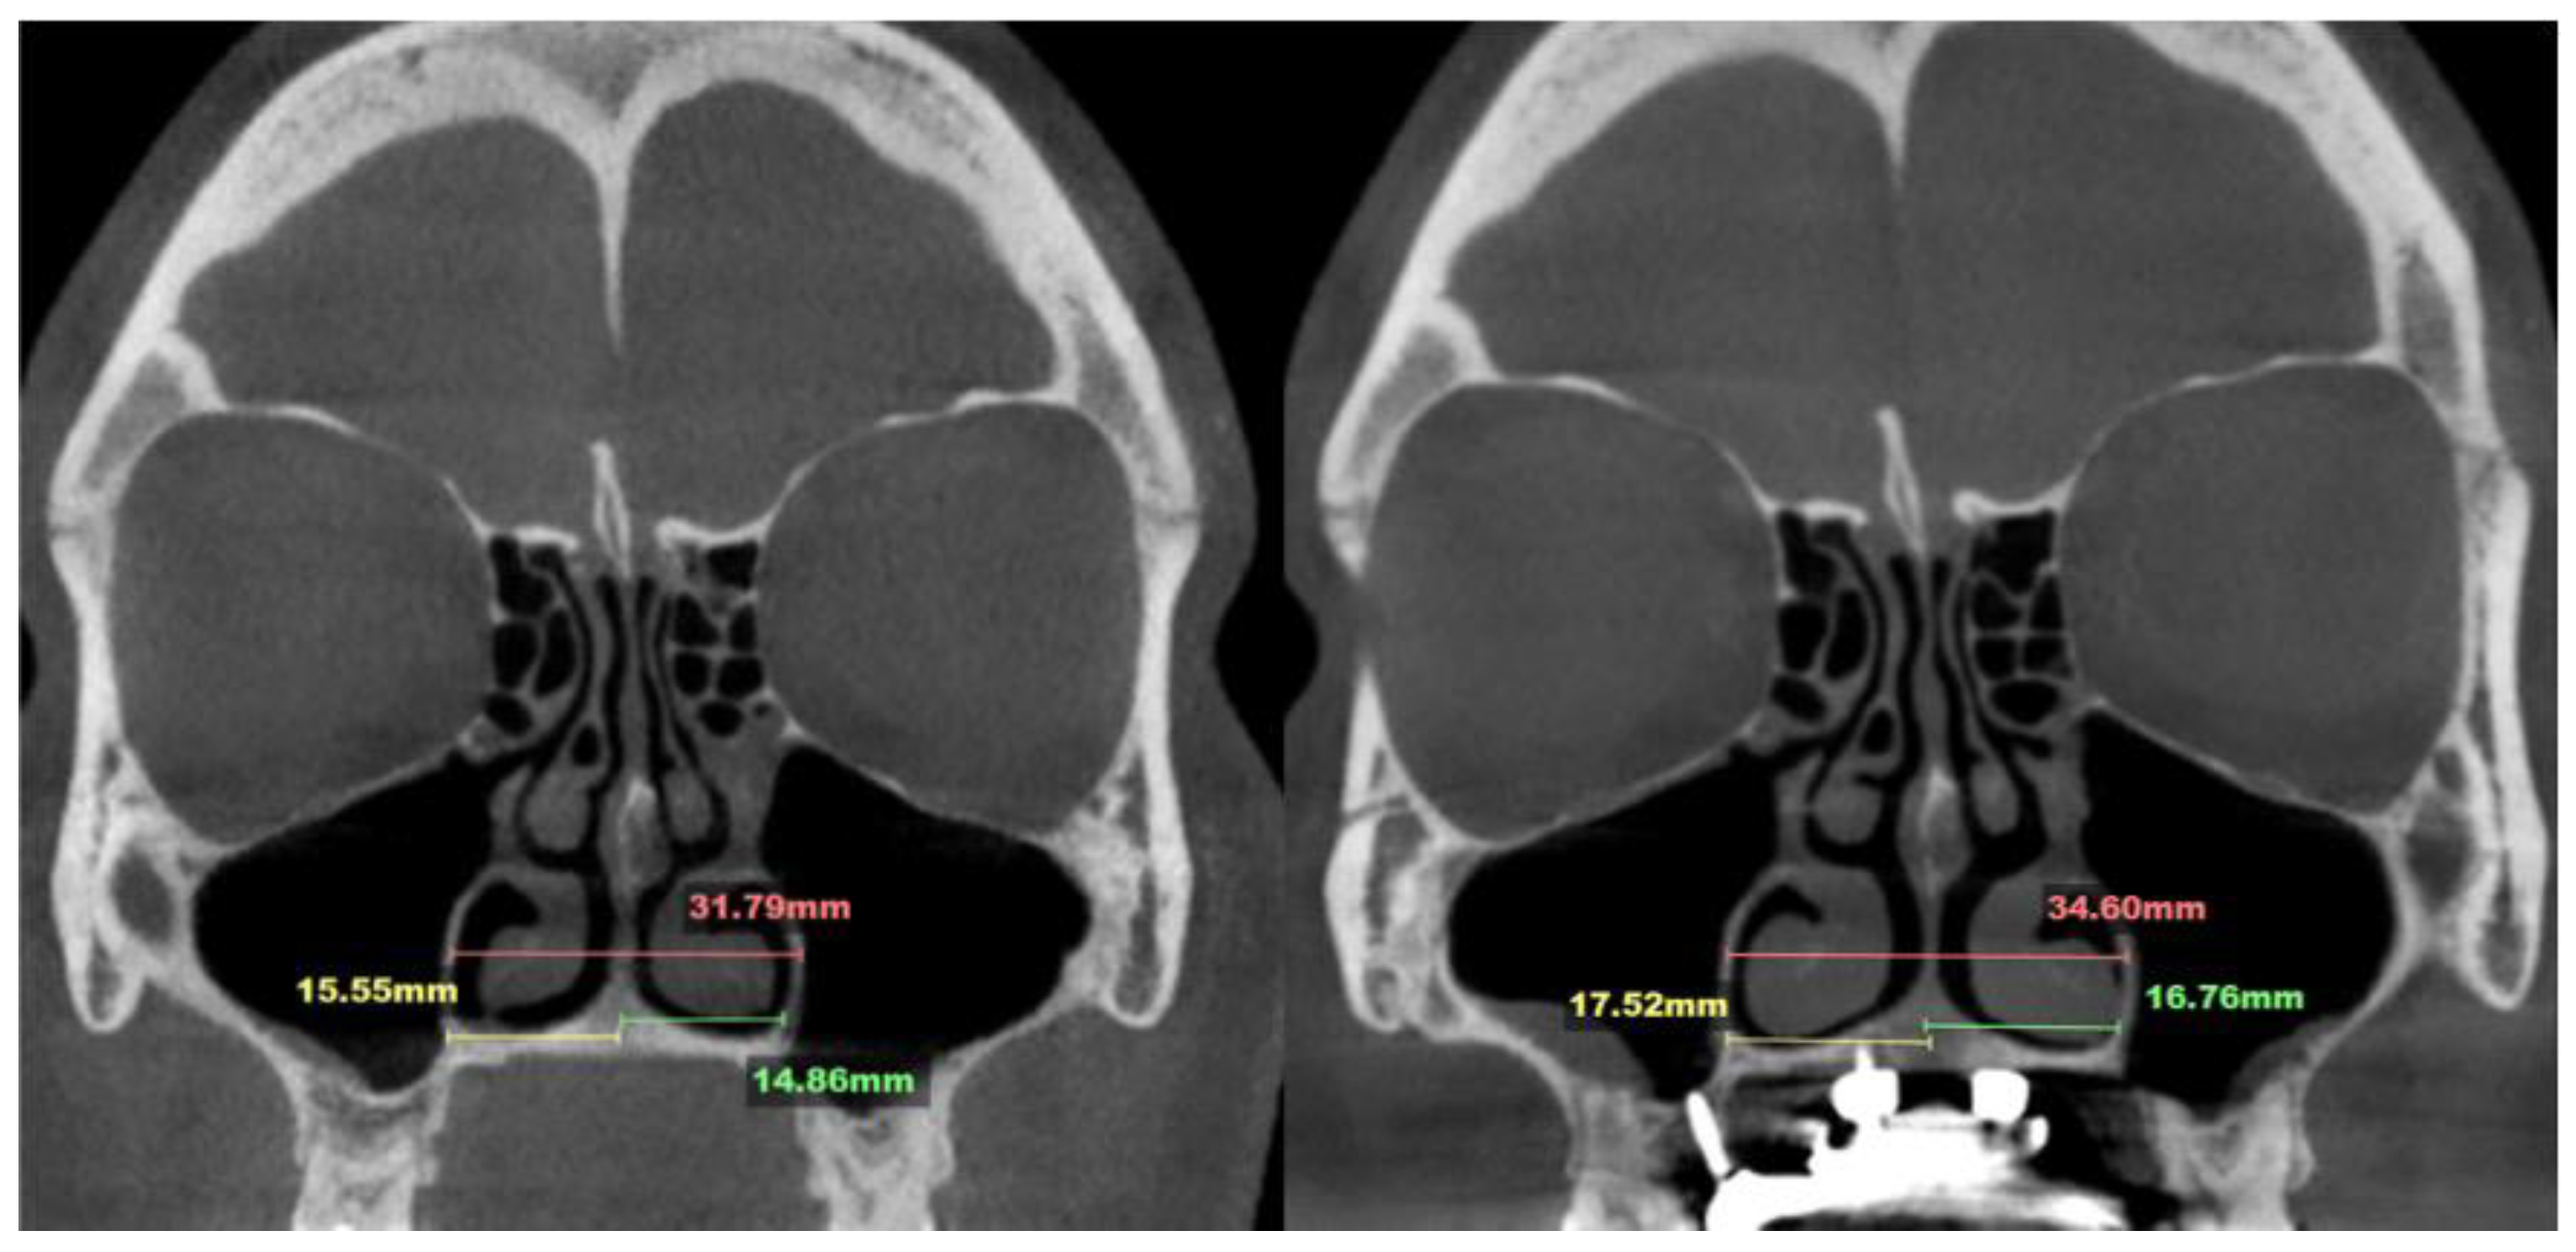

2.7. Case D: Midfacial Asymmetry Correction with Guided Expansion

- Asymmetric expansion with residual attachment of the nasal septum unilaterally to the maxillary crestal bone (Figure 5,6);

- Diagonal fractures of the palatine bone extending from the distal margin of the palatal process of the maxillary bone unilaterally, often associated with pain and tension;

- Asymmetric displacement of the nasal base floor with unilateral downward and outward movement (Figure 5,6)

- Downward inclination and displacement of the alveolar process on the ipsilateral side (Figure 5,6);

- Unilateral soft tissue shift, including nasal ala and corner of the mouth displacement toward the side of unattached separation.